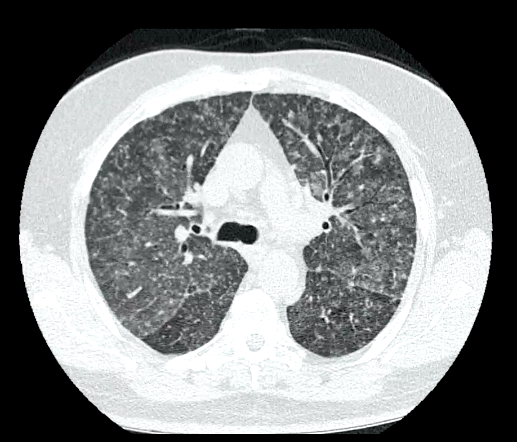

Miliary TB shown, nodular opacities, with diffuse spread of mycobacterium throughout the lung tissue (this will also be spread diffusely throughout other body tissues).

CT scan will show this even more distinctly.